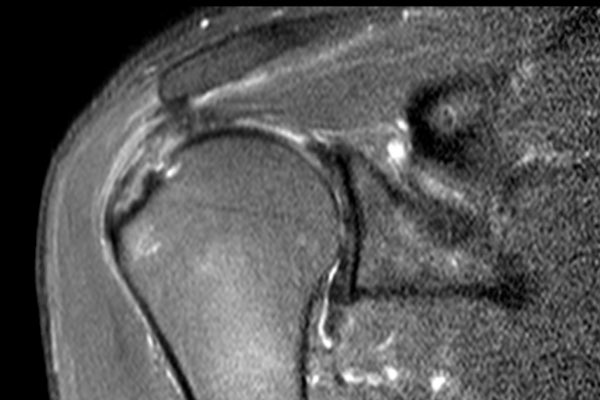

Rách toàn bộ chiều dày

Rách toàn bộ chiều dày (Full Thickness Tear – FTT) là tổn thương kéo dài từ mặt túi hoạt dịch (bursal surface) xuyên suốt đến mặt khớp (articular surface).

Rách toàn bộ chiều dày được phân loại thành:

- FTT không hoàn toàn (Incomplete FTT)

Có rách toàn bộ chiều dày nhưng chỉ một phần chiều rộng của gân bị tổn thương. - FTT hoàn toàn (Complete FTT)

Rách toàn bộ chiều dày được gọi là hoàn toàn khi toàn bộ gân bị đứt. - FTT hoàn toàn + co rút (Complete FTT + retraction)

FTT có biến chứng co rút cơ. - FTT hoàn toàn + co rút + teo cơ (Complete FTT + retraction + atrophy)

FTT có biến chứng co rút cơ, teo cơ và thâm nhiễm mỡ, dẫn đến tiên lượng xấu.

Rách toàn bộ chiều dày hoàn toàn

Nhấp vào hình ảnh để phóng to, sau đó cuộn qua các lát cắt.

Có hình ảnh rách toàn bộ chiều dày gân cơ trên gai kèm co rút và teo cơ.

Lưu ý các dải mỡ trong cơ tròn bé, cơ trên gai và cơ dưới gai.